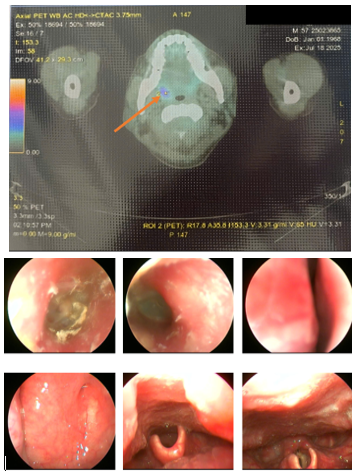

3. Hình ảnh tăng chuyển hóa FDG ở amidam bên phải (SUVmax: 3.71) Đối chiếu với nội soi.

Hình 2. Hình ảnh tăng chuyển hóa FDG ở amidam bên phải với SUVmax: 3.71 (được ký hiệu bằng mũi tên màu da cam, hình trên). Tuy nhiên, khi đối chiếu với hình ảnh nội soi tai mũi họng lại không có tổn thương nghi ngờ ác tính (Hình dưới).

Nội soi tai mũi họng: Nấm ống tai ngoài bên trái. Chưa phát hiện tổn thương nghi ngờ ác tính các vùng khoang mũi, miệng, họng, thanh quản, ống 2 bên.

Hình 6. Hình ảnh nội soi tai mũi họng chưa phát hiện tổn thương nghi ngờ ác tính (Tai Phải: Ống tai ngoài có mảng trắng dạng nấm, Màng nhĩ dày đục; Tai trái: Màng nhĩ dày đục; Mũi: Khe sàn mũi sạch, cuốn mũi 2 bên bình thường; Vòm họng: Nhẵn, sạch, cân đối; Họng: Sạch; Thanh quản: Dây thanh 2 bên nhẵn, di động bình thường.) Mặc dù đối chiếu với PET/CT có tổn thương tăng bắt FDG tại amidan bên phải (SUVmax:3.71)

Hình 7. Hình ảnh nội soi thực quản-dạ dày chưa phát hiện tổn thương nghi ngờ ác tính

Hình 8. Hình ảnh nội soi đại tràng chưa phát hiện tổn thương nghi ngờ ác tính